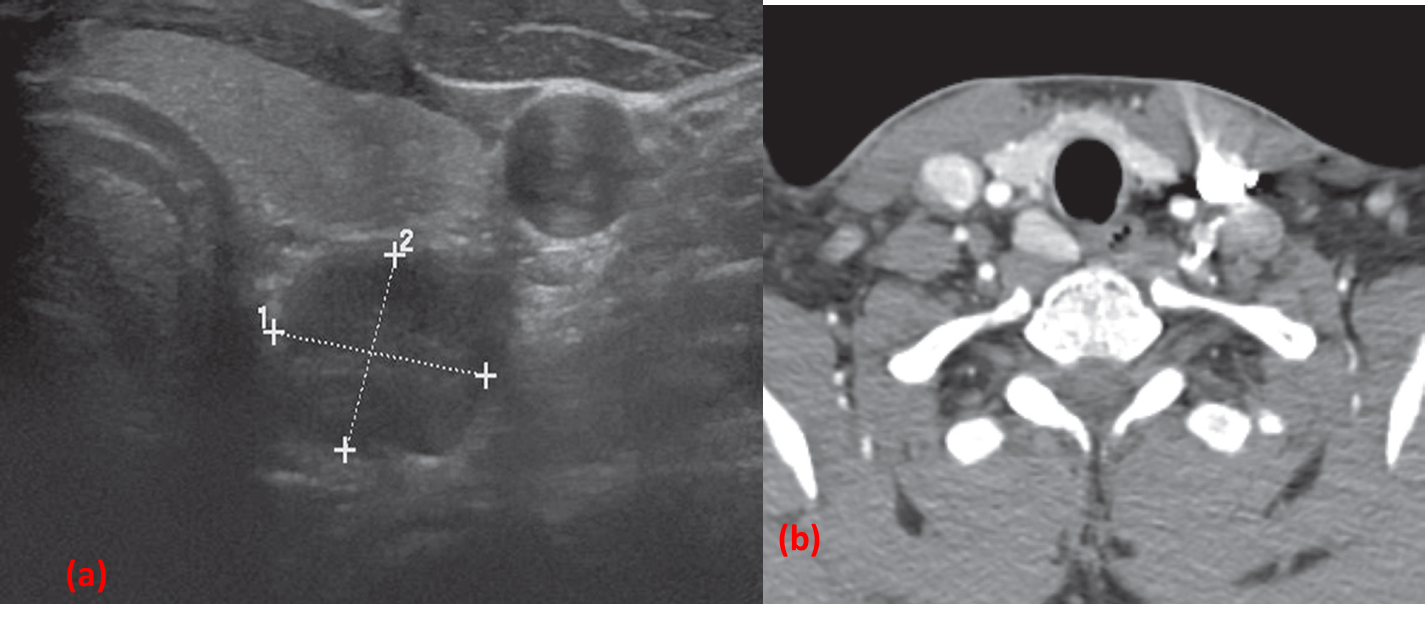

(a) Transverse ultrasound of a parathyroid adenoma (calipers) seen behind the left lobe of the thyroid gland . The common carotid artery is also demonstrated.

(b) CT of another patient showing an avidly enhancing right parathyroid adenoma.